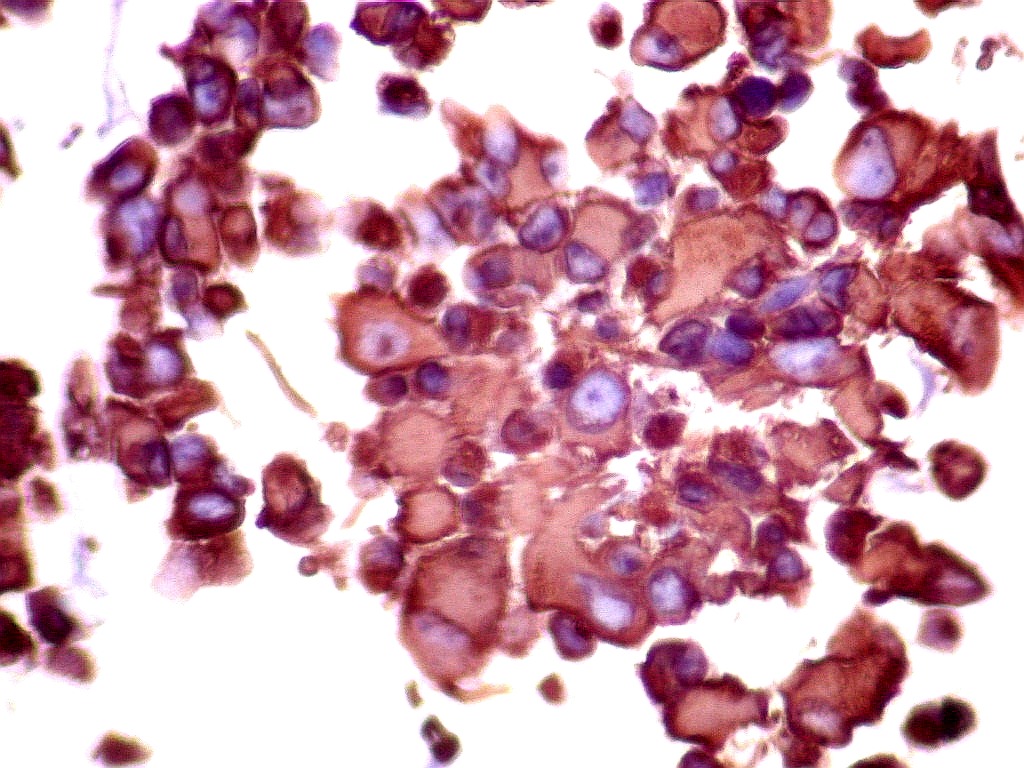

Tumor teratóide rabdóide atípico de III ventrículo.

GFAP.     O filamento intermediário do citoesqueleto que caracteriza os astrócitos é forte e difusamente positivo nas células neoplásicas deste tumor teratóide-rabdóide atípico.  Indica diferenciação astrocitária no tumor.  O folículo linfóide e vasos proliferados são negativos.  O epêndima  do III ventrículo, onde o tumor está localizado, também é GFAP positivo.